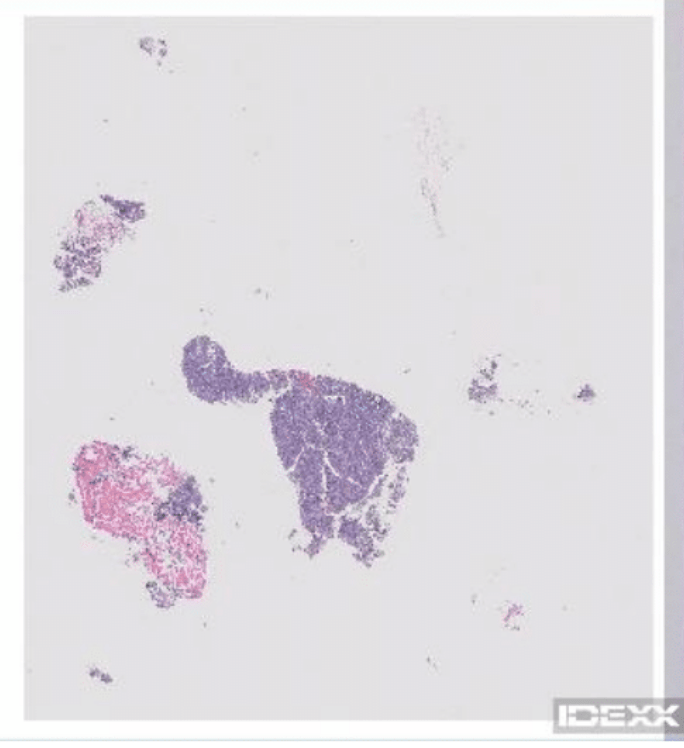

Histology gave us the grave news: B cell spinal lymphoma. My heart dropped. His diagnosis was emotionally draining.

I struggled to find reliable scientific literature describing and treating feline spinal cancers. From the very few papers that I found, most cats with this diagnosis had survival day 1 from the diagnosis. That meant euthanasia. I could not do it. I was not ready to give up him. Scientific papers had very few notes which cats survived and which ones did not. This meant only one thing, even the veterinarians were going blind.

The staff oncologist strongly pushed for a CHOP protocol, a combination chemotherapy consisting of cyclophosphamide, hydroxydaunorubicin hydrochloride (doxorubicin hydrochloride), vincristine and prednisone. I was mentally drained, I said yes. I could not find any valid scientific evidence for anything better.